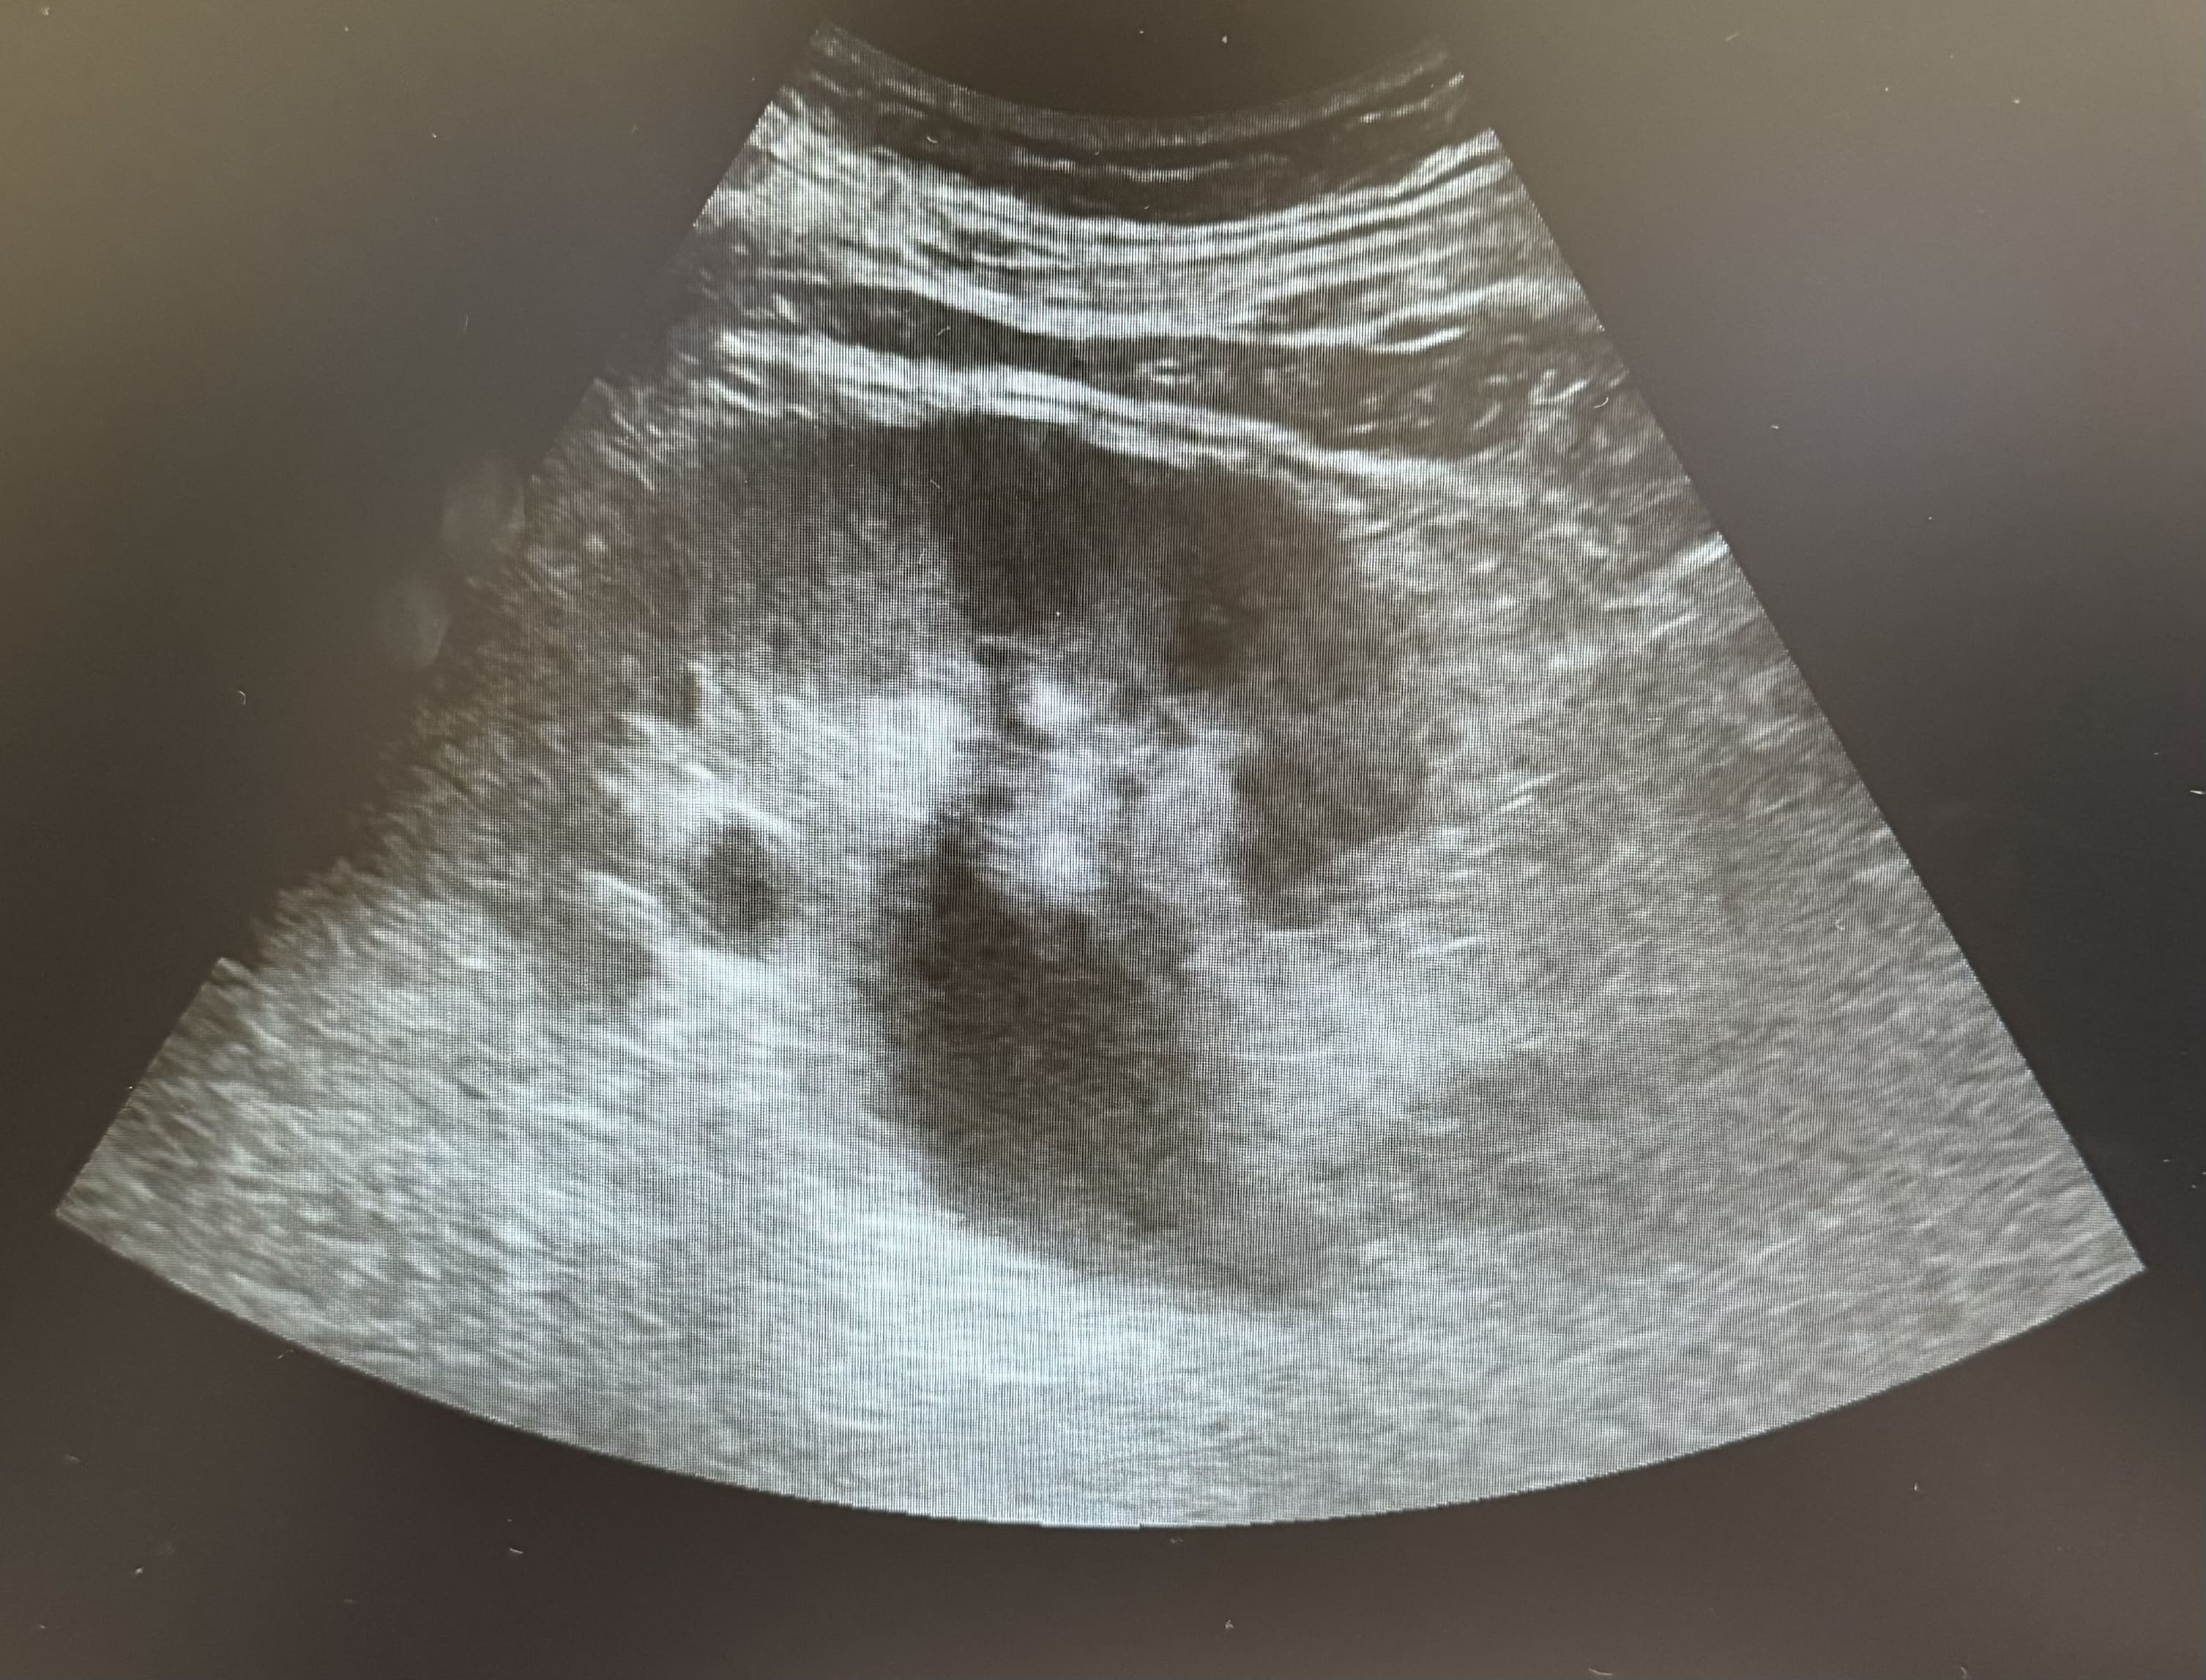

Hombre de de 73 años que acude a consulta de urgencias por dolor en fosa renal derecha desde hace 2 semanas irradiado hacia hemiabdomen derecho. En ese contexto pérdida de control de esfínter con escapes de orina especialmente nocturnos. Refiere además desde hace dos meses dificultad para el inicio de la micción, polaquiuria y nicturia asociadas sin disuria. Sin fiebre ni sensación distérmica en domicilio. No otra clínica por sistemas o aparatos.

La ecografía POCUS es una herramienta de gran valor en situaciones de emergencia y en el ámbito de la medicina de familia. Su uso permite un diagnóstico rápido de la retención urinaria, la evaluación del estado renal (hidronefrosis) y la identificación de la causa subyacente (hipertrofia prostática). Además, facilita intervenciones inmediatas y permite el seguimiento continuo en pacientes con enfermedades crónicas del tracto urinario.